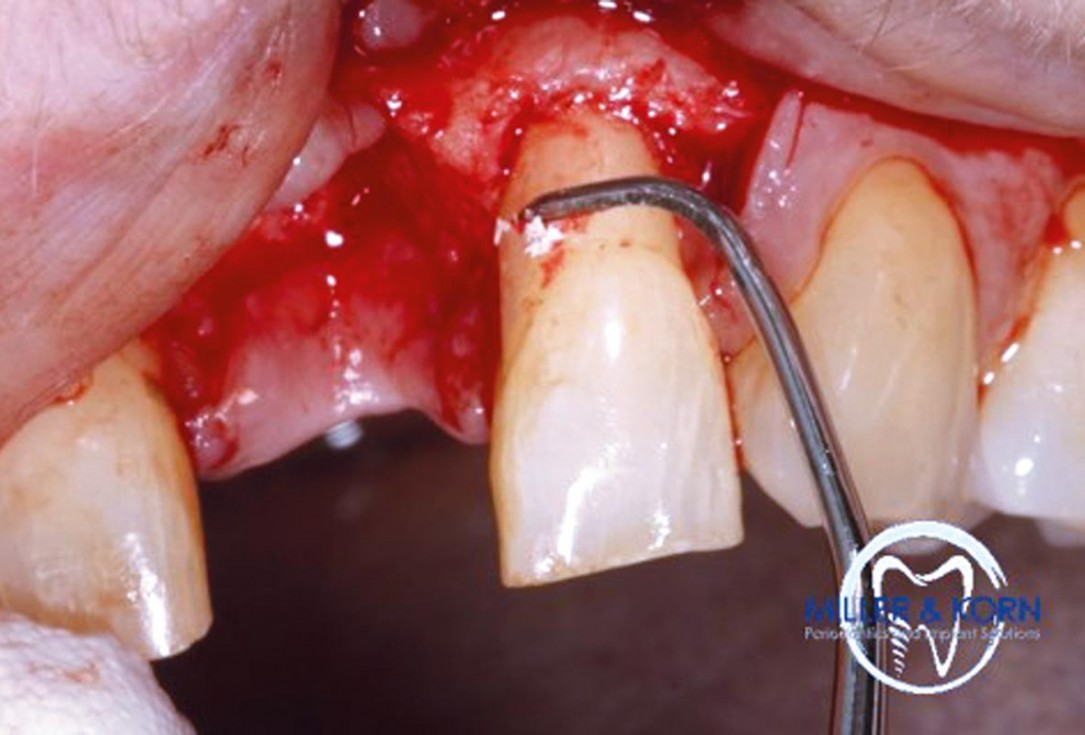

06/39 - Root planning of the adjacent teethImmediate implant placement and correction of horizontal and vertical bone loss using an allograft bone ring, cerabone® and Jason® membrane - Drs. Miller and Korn